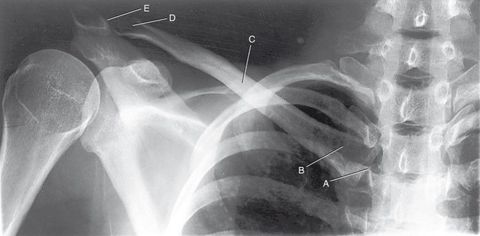

Question Answer

A. sternoclavicular joint (SC) B. sternal extremity C. body D. acromial extremity E. acromioclavicular joint (AC)